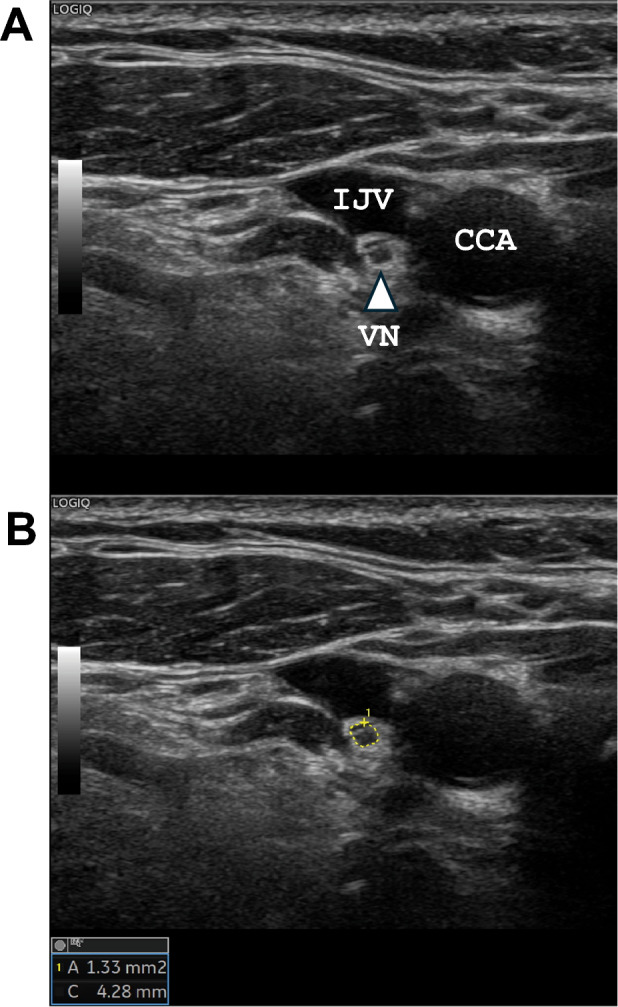

Ultrasound was performed to evaluate the CSA of the VN using a LOGIQTME9 XD clearTM2.0 (GE Healthcare, Wauwatosa, WI, USA) with a 10–15 MHz linear array transducer. Ultrasonography and measurements of the CSA of the VN were performed by one of three experienced technicians (T.N., F.E., and A.H.) who were certified by the Japan Academy of Neurosonology. Cross-sectional imaging of the VN was recorded bilaterally at the level of the thyroid gland. The VN was identified within the carotid sheath between the internal jugular vein and the carotid artery, with the transducer placed transversely on the lateral neck (Fig. 1A). During the study, all subjects were placed in a supine position and rotate their heads away from the scanning side. The CSA of the VN was obtained using the trace method, measuring along the inner aspect of the hyperechoic epineurium (Fig. 1B). The CSA of the VN (right VN and left VN) was measured twice by technicians, and the mean CSA was calculated. Between each measurement, echo transducer was completely removal. The intraclass correlation coefficient (ICC) (1, 2) was consistently high for each technician (T.N.: n = 125, 0.956 for right VN, 0.938 for left VN; F.E.: n = 43, 0.776 for right VN, 0.828 for left VN; A.H.: n = 28, 0.937 for right VN, 0.878 for left VN). For the interrater correlation, ICC (2.1) for the CSA of the VN was calculated for 10 patients in a preliminary study using a different cohort as follows: between T.N. and A.H., 0.878 for right VN and 0.823 for left VN; between T.N. and F.E., 0.922 for right VN and 0.928 for left VN.

Fig. 1.

Ultrasonographic image of the vagus nerve (VN). The right VN is shown as a small, rounded, hypoechoic structure between the common carotid artery (CCA) and the internal jugular vein (IJV) (A, triangle arrow). The cross-sectional area of the VN was measured by manual tracing (B, yellow circle)